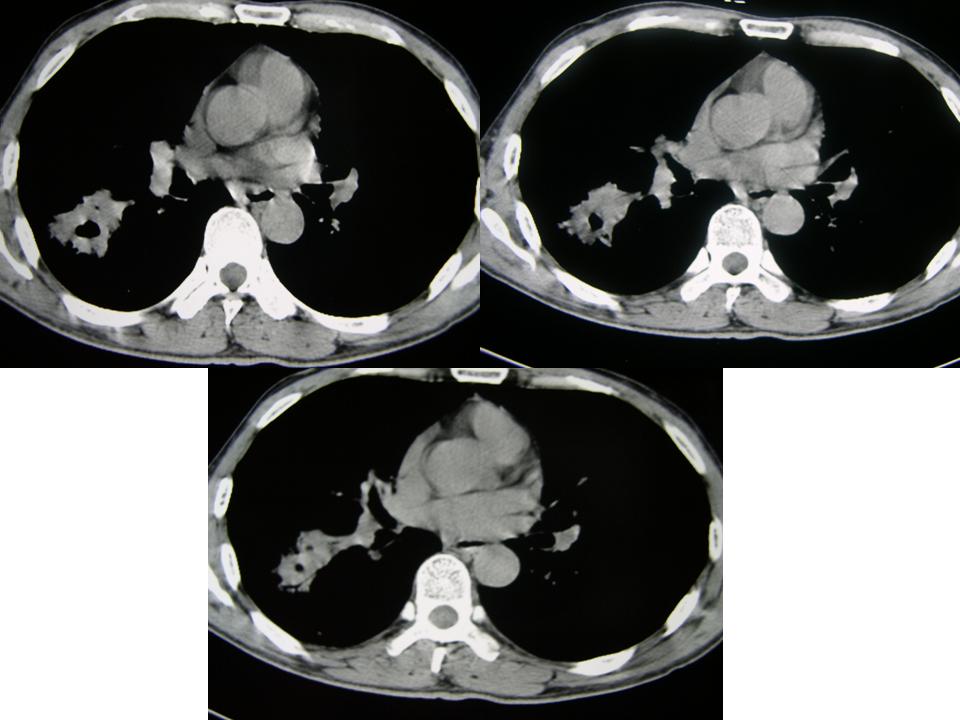

男性,65岁。主诉:干咳5年,加重月余。5年中多次发作,每次持续时间长短不一,静脉滴注缓解;近月余加重,用药效果差。晨起加重,痰少,无发热,无血丝

右肺下叶实质性肿块,边缘毛刺,内见偏心空洞。支持:周围性肺癌!

2、右下肺叶团片状影,见空泡征、分叶征、毛刺征及偏心性空洞,符合肺癌(腺癌可能性大)

考虑右肺下叶周围型肺癌(癌性空洞形成)并阻塞性肺炎。

病理结果:

谢楼主反馈病理结果(右肺下叶炎性病变伴小脓肿形成)。